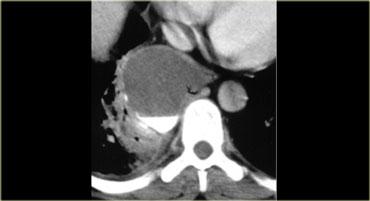

Hãy mô tả hình ảnh bên trái.

Sau đó tiếp tục.

CT cho thấy một khối nằm ở trung thất trước.

Khối có dạng nang nhưng có các thành phần đặc ngấm thuốc cản quang, do đó cần lo ngại đến u lympho, u tế bào mầm và u tuyến ức dạng nang.

Trường hợp này được xác định là u tuyến ức dạng nang.